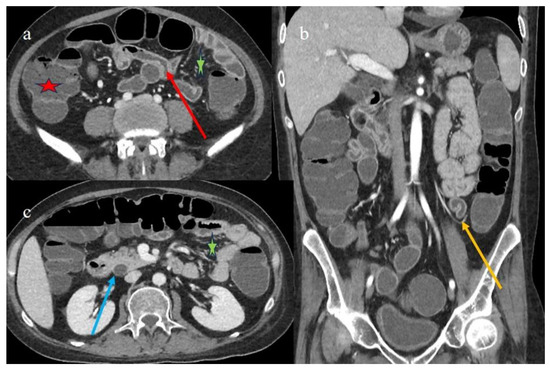

| 1 | P | P | Multisegmental and plurifocal parietal thickness with homogeneous mucosal enhancement on distal ileus | Multisegmental thickness with homogeneous mucosal enhancement | Mild diffuse comb sign and poor reactive mesenteric lymph node | Splenic infarct |

| 2 | P | P | Diffuse parietal thickness with stratified enhancement | Multisegmental thickness with homogeneous mucosal enhancement | Diffuse comb sign and poor reactive mesenteric lymph node | Mild gallbladder thickness and mild biliary tract dilatation |

| 3 | P | P | Multisegmental thickness with stratified enhancement at the terminal ileus (on CECT control at 92 days). The CECT control at 129 days showed persistence of mild parietal thickness at terminal ileus and with mucosal enhancement | Diffuse parietal thickness with stratified enhancement (On CECT control at 92 days) The CECT control at 129 days showed colic fluid distension with mild diffuse mucosal enhancement | Diffuse comb sign, mild ascites, and poor reactive mesenteric lymph node | Hepatomegaly and mild gallbladder thickness |

| 4 | P | P | Intestinal diffuse homogeneous thickness with homogeneous mucosal enhancement (on CECT control at 66 days after the HSCT); diffuse small bowel involvement with increased parietal thickness on CECT control at 120 days | Appearance of multisegmental thickness on sigma and descending colon and stratified enhancement on transverse colon on the CT FU at 120 days | Diffuse comb sign and poor reactive mesenteric lymph node | Mild gallbladder thickness and persistence of biliary tract dilatation on follow-up CT |

| 5 | P | P | Multisegmental thickness with stenosis on jejunal loops and SBO and segmental and focal thickness on the terminal ileus and appendix | Diffuse parietal thickness with stratified enhancement | Mild comb sign, poor reactive mesenteric lymph node, small air bubbles in the ascites | Small splenic areas of ischemia |